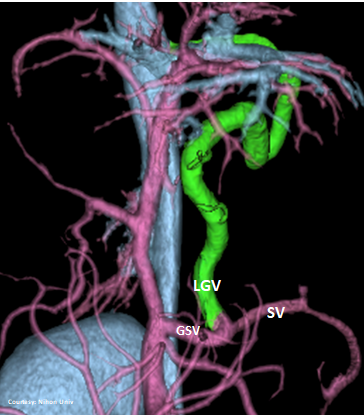

Does LEFT GASTRIC VEIN (LGV) enter the GASTROSPLENIC VEIN (GSV)?

slide10